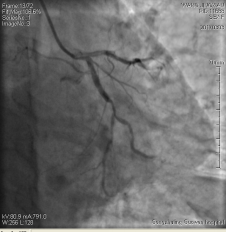

3月3日14時(shí)30分:經(jīng)右橈動(dòng)脈行冠脈造影見:左主干未見明顯異常,TIMI血流3級(jí),前降支開口正常,近中段20%狹窄,TIMI血流3級(jí);回旋支開口正常,中遠(yuǎn)段75%狹窄,TIMI血流3級(jí)。右冠狀動(dòng)脈開口正常,中段長病變,最重99%狹窄, TIMI血流3級(jí)。

圖1 回旋支遠(yuǎn)段70%狹窄 圖2 右冠脈中段99%狹窄